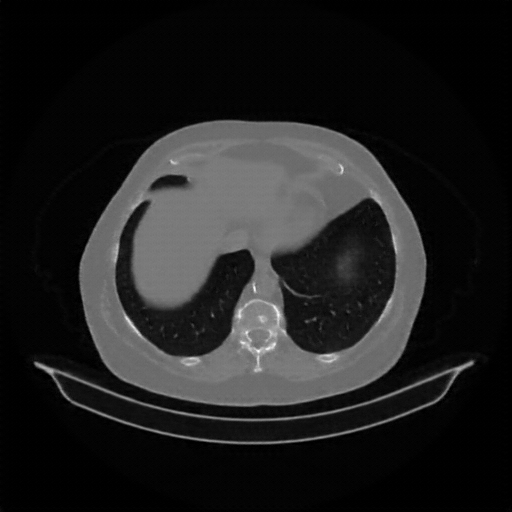

Original VENOUS CT scan

Full window (WL 1023.5, WW 4095 β†’ Low βˆ’1024, High +3071)

Actual HU range: [-1024.0, 1092.0]